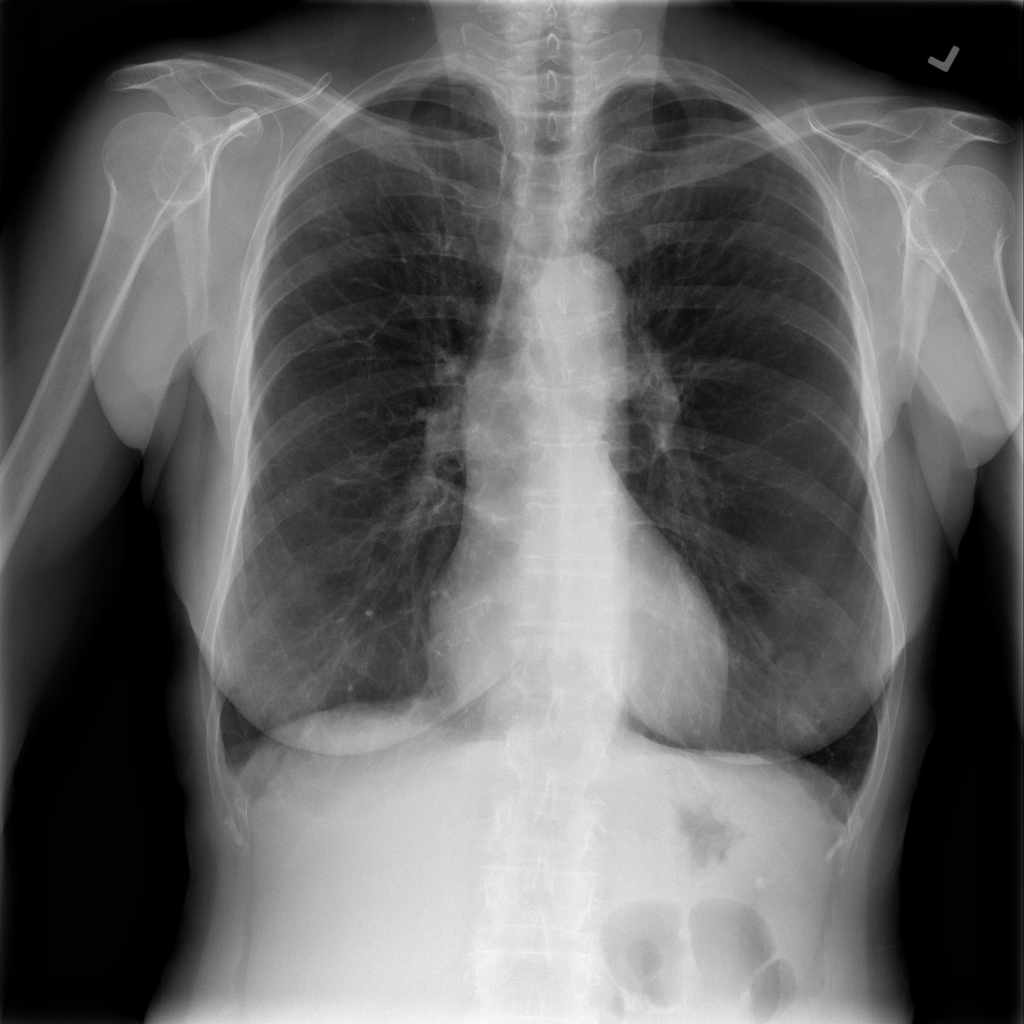

PAT-1F50 · IMG-000Fibrosis

PAT-1F50 · IMG-000

PA